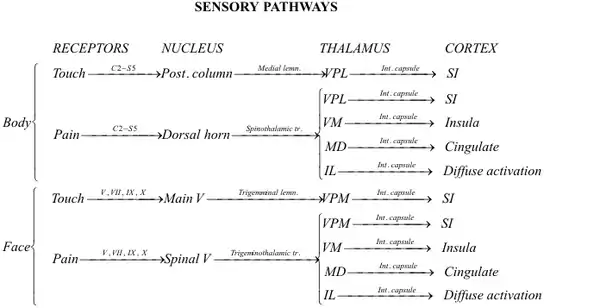

Sensory pathways

Sensory pathways from the periphery to the cortex are separate for touch-position and pain-temperature sensations. All sensory information is sent to specific nuclei in the thalamus. Thalamic nuclei, in turn, send information to specific areas in the cerebral cortex. Each pathway consists of three bundles of nerve fibers connected in series:

The secondary neurons in each pathway decussate (cross the spinal cord or brainstem), because the spinal cord develops in segments. Decussated fibers later reach and connect these segments with the higher centers. The optic chiasm is the primary cause of decussation; nasal fibers of the optic nerve cross (so each cerebral hemisphere receives contralateral—opposite—vision) to keep the interneuronal connections responsible for processing information short. All sensory and motor pathways converge and diverge to the contralateral hemisphere.[5]

Although sensory pathways are often depicted as chains of individual neurons connected in series, this is an oversimplification. Sensory information is processed and modified at each level in the chain by interneurons and input from other areas of the nervous system. For example, cells in the main trigeminal nucleus (Main V in the diagram below) receive input from the reticular formation and cerebellar cortex. This information contributes to the final output of the cells in Main V to the thalamus.

Touch-position information from the body is carried to the thalamus by the medial lemniscus, and from the face by the trigeminal lemniscus (both the anterior and posterior trigeminothalamic tracts). Pain-temperature information from the body is carried to the thalamus by the spinothalamic tract, and from the face by the anterior division of the trigeminal lemniscus (also called the anterior trigeminothalamic tract).

Pathways for touch-position and pain-temperature sensations from the face and body merge in the brainstem, and touch-position and pain-temperature sensory maps of the entire body are projected onto the thalamus. From the thalamus, touch-position and pain-temperature information is projected onto the cerebral cortex.

Summary

The complex processing of pain-temperature information in the thalamus and cerebral cortex (as opposed to the relatively simple, straightforward processing of touch-position information) reflects a phylogenetically older, more primitive sensory system. The detailed information received from peripheral touch-position receptors is superimposed on a background of awareness, memory and emotions partially set by peripheral pain-temperature receptors.

Although thresholds for touch-position perception are relatively easy to measure, those for pain-temperature perception are difficult to define and measure. "Touch" is an objective sensation, but "pain" is an individualized sensation which varies among different people and is conditioned by memory and emotion. Anatomical differences between the pathways for touch-position perception and pain-temperature sensation help explain why pain, especially chronic pain, is difficult to manage.

Touch-position sensation

Touch-position information from the body is sent to the ventral posterolateral nucleus (VPL) of the thalamus. Touch-position information from the face is sent to the ventral posteromedial nucleus (VPM) of the thalamus. From the VPL and VPM, information is projected to the primary somatosensory cortex (SI) in the parietal lobe.

The representation of sensory information in the postcentral gyrus is organized somatotopically. Adjacent areas of the body are represented by adjacent areas in the cortex. When body parts are drawn in proportion to the density of their innervation, the result is a "little man": the cortical homunculus.

Pain-temperature sensation

Pain-temperature information is sent to the VPL (body) and VPM (face) of the thalamus (the same nuclei which receive touch-position information). From the thalamus, pain-temperature and touch-position information is projected onto SI.

Unlike touch-position information, however, pain-temperature information is also sent to other thalamic nuclei and projected onto additional areas of the cerebral cortex. Some pain-temperature fibers are sent to the medial dorsal thalamic nucleus (MD), which projects to the anterior cingulate cortex. Other fibers are sent to the ventromedial (VM) nucleus of the thalamus, which projects to the insular cortex. Finally, some fibers are sent to the intralaminar nucleus (IL) of the thalamus via the reticular formation. The IL projects diffusely to all parts of the cerebral cortex.

The insular and cingulate cortices are parts of the brain which represent touch-position and pain-temperature in the context of other simultaneous perceptions (sight, smell, taste, hearing and balance) in the context of memory and emotional state. Peripheral pain-temperature information is channeled directly to the brain at a deep level, without prior processing. Touch-position information is handled differently. Diffuse thalamic projections from the IL and other thalamic nuclei are responsible for a given level of consciousness, with the thalamus and reticular formation "activating" the brain; peripheral pain-temperature information also feeds directly into this system.